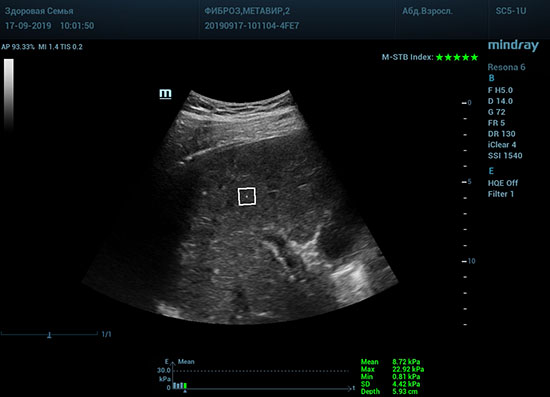

Определение плотности печени. Не ошибся ли оператор при измерении эластических свойств печени? Для оценки критериев качества предусмотрен индекс MBT, который покажет насколько «твердой» была рука оператора и двигалась ли печень. При MBT 5* рука тверда и показатели достоверны. Для оценки качества результатов используется IQR индекс, отображающий колебания показателей в точке измерения при расчете медианы. Показатели при IQR <30% считаются приемлемыми. Техника сканирования через межреберные промежутки требует размещение окна интереса на несколько сантиметром ниже капсулы, для исключения эффекта реверберации. Установка ROI на паренхиму без захвата сосудов, для исключения погрешностей измерения.

Стадия фиброза определяется по системе METAVIR Staging, построенной на данных биопсии и сопоставлении с данными эластографии. Своевременная диагностика фиброза, и начало его лечения, залог благоприятного исхода заболевания.